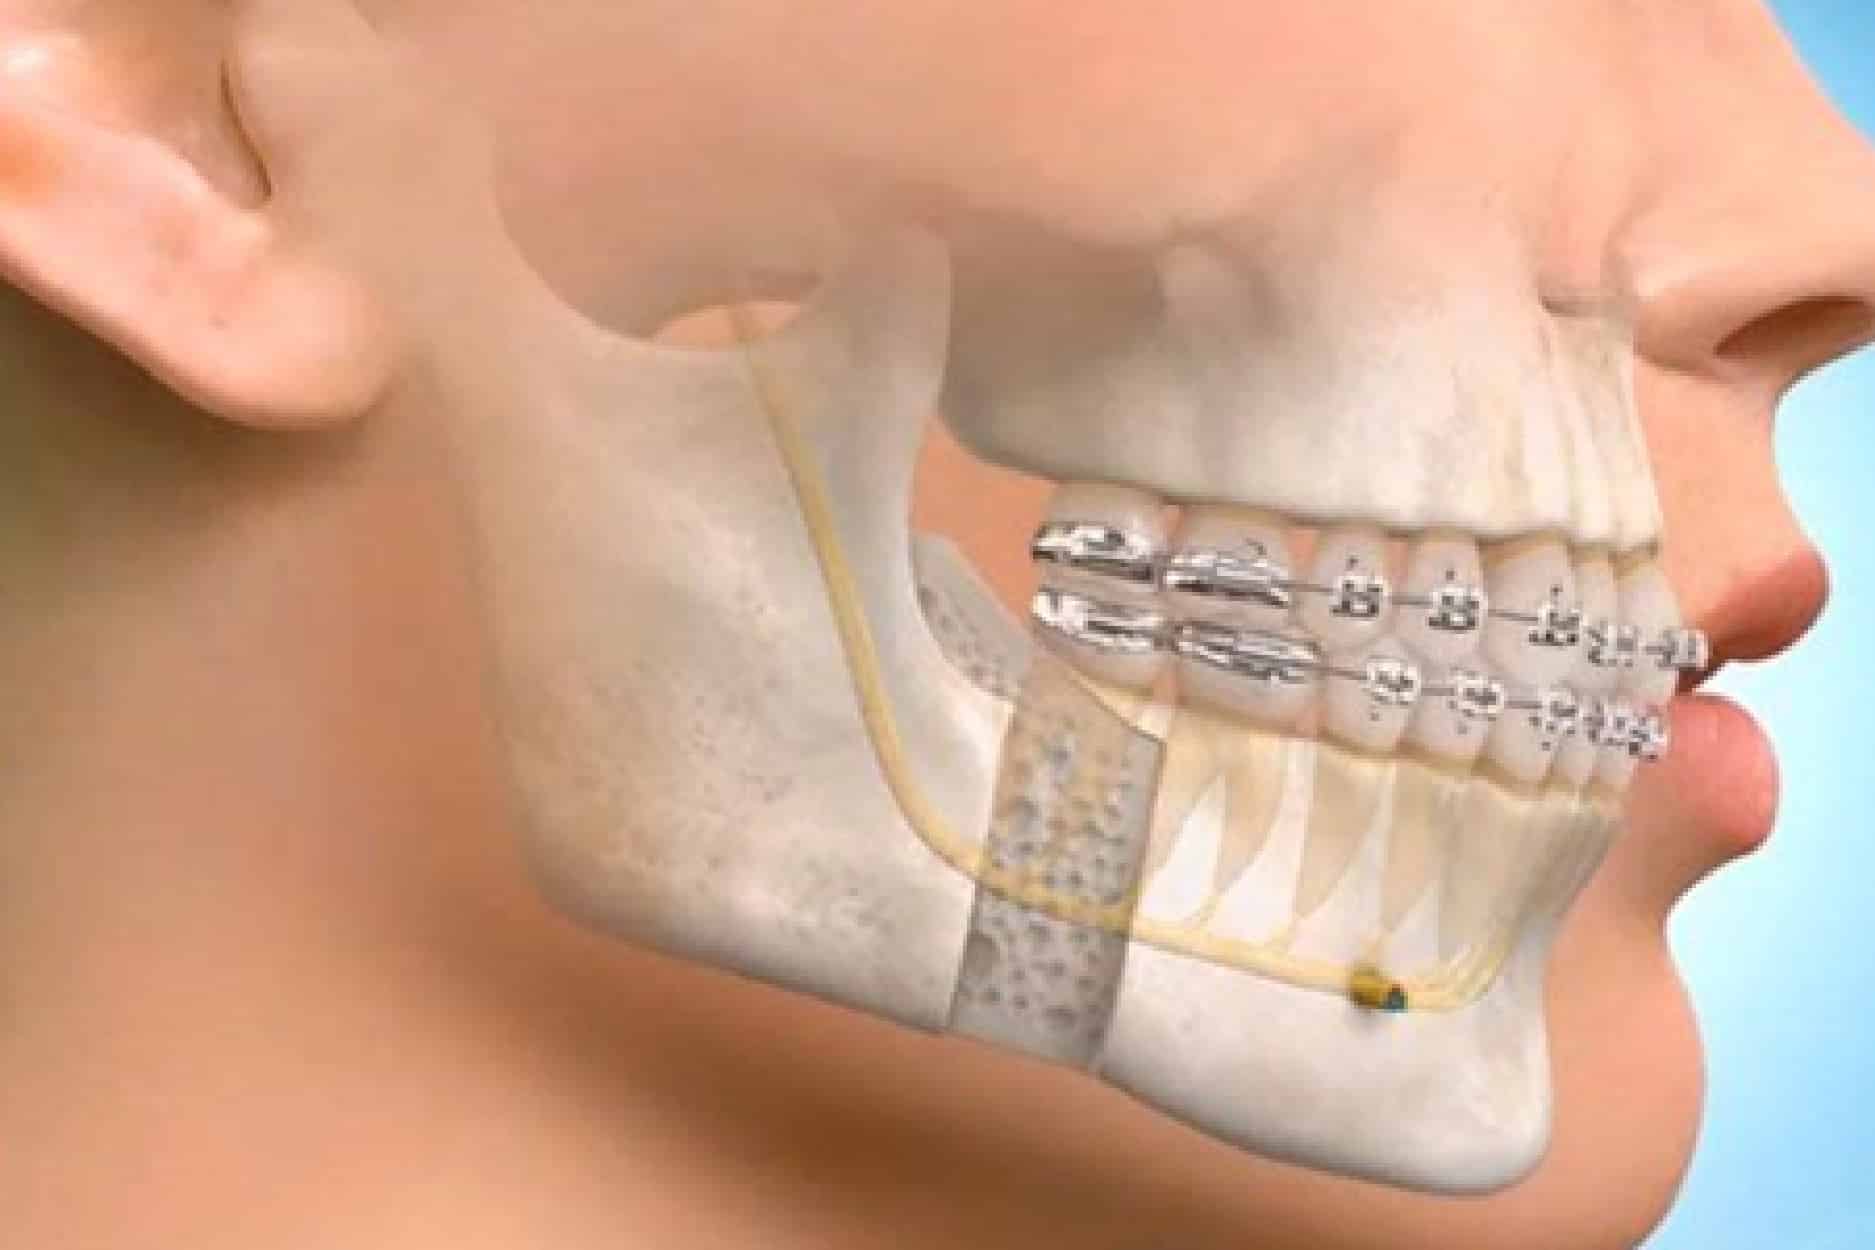

Oral & Maxillofacial Surgery involves complex surgical treatments affecting the mouth, jaw, face, and neck. These procedures require highly accurate coding, detailed documentation, and strict compliance with insurance guidelines. Our specialized billing services are designed to manage surgical claims efficiently while maximizing reimbursements and minimizing denials.

- Jaw correction & bite assessment billing

From routine extractions to complex surgical interventions, oral surgery billing demands precision and payer-specific expertise. Our billing professionals ensure that impacted tooth removal, implant placement, cyst removal, and anesthesia services are coded accurately and submitted promptly.